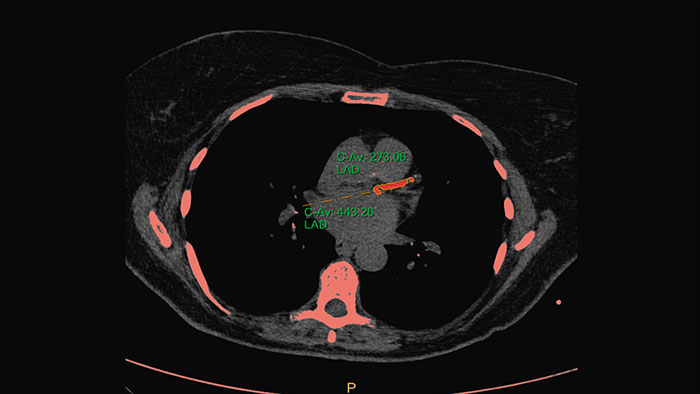

One-click 3D calcium segmentation

One-click 3D segmentation and quantification for coronary arteries calcifications including mass, Agatston, and volume scores.